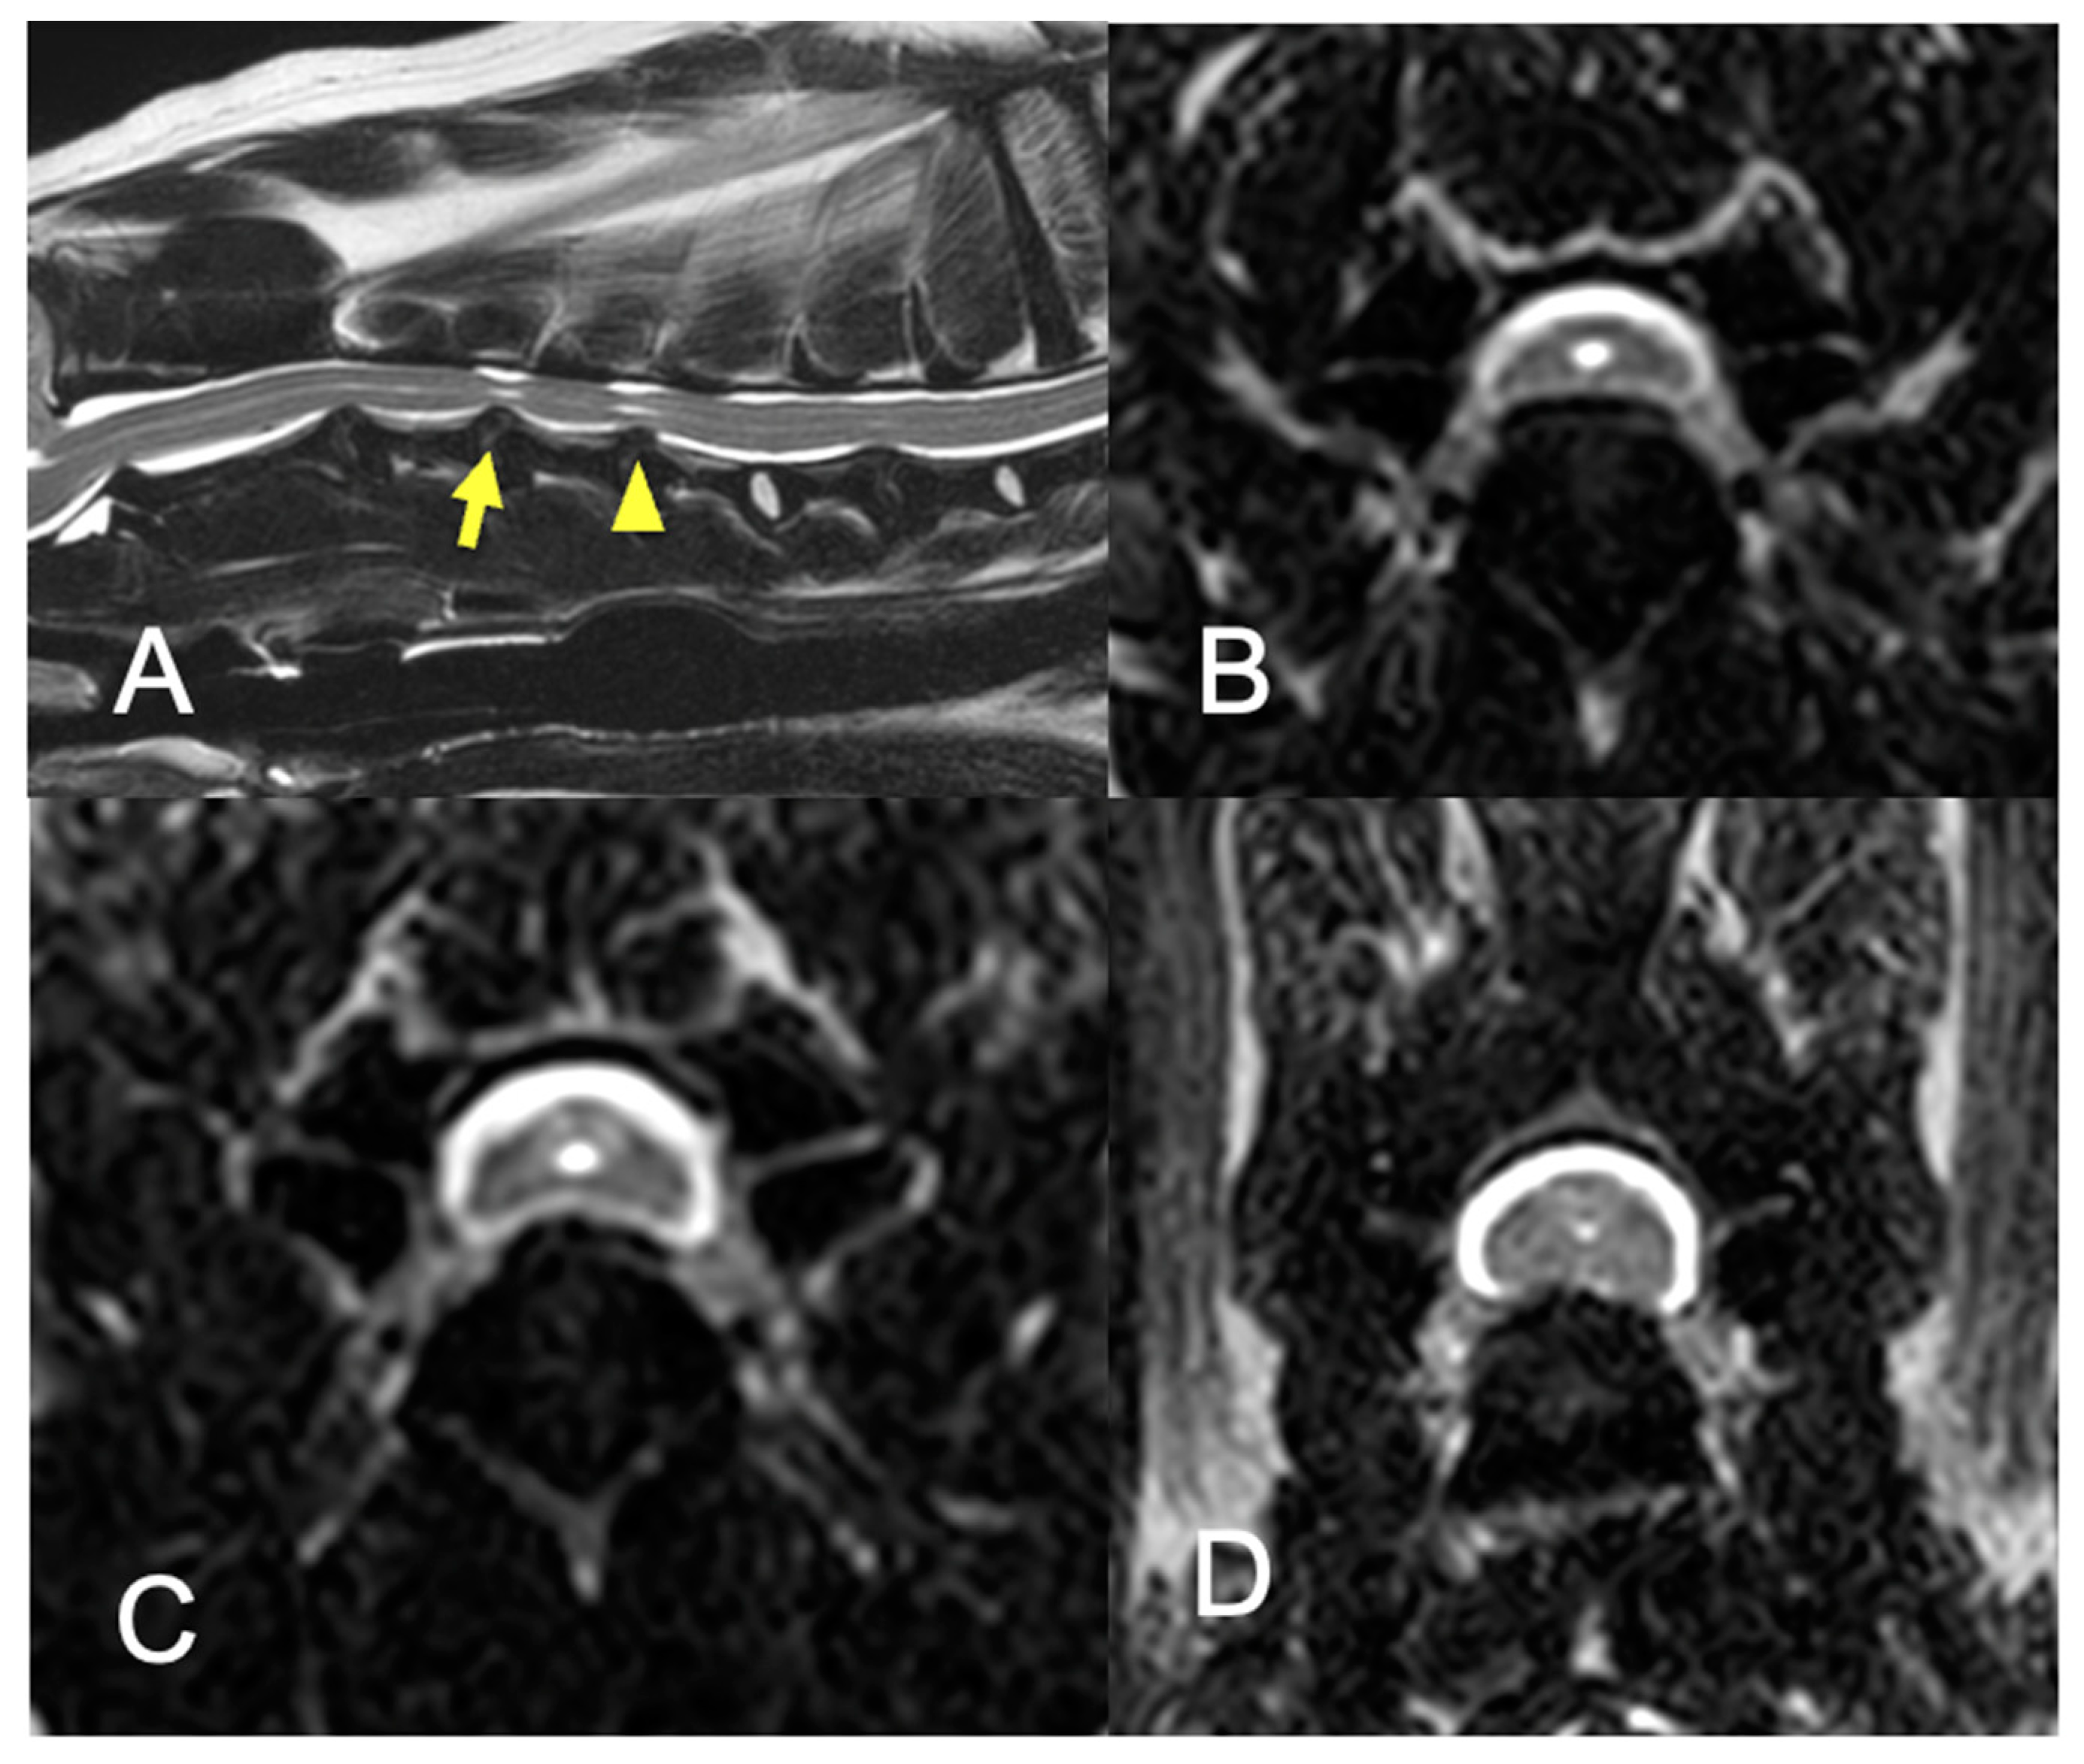

2.2. Imaging

2.6. Imaging Analyses

3.4. Morphometric Analyses